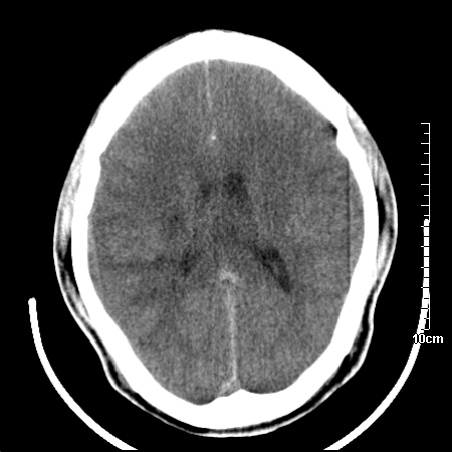

头晕.头痛间断意识恍惚1周 m/21y

4天上述症状加重伴左侧肢体发软,复查ct,

右侧放射冠可见点状低密度,可疑腔隙性梗塞

右側放射冠区改变,建议ct增强或mri检查.

右側额叶、放射冠区灰白质改变,建议ct增强或mri检查

右侧基底节区低密度灶,建议磁共振检查。

右侧放射冠区混杂密度灶,边缘不清,病人较年轻,结合有发热病史,支持感染性病变,建议密切结合临床可抗感染治疗后复查。

右侧颞叶病变定性困难,既然发病急,又有发热,脑脓肿不能除外。

右侧颞叶混杂密度灶,强烈建议:增强ct检查